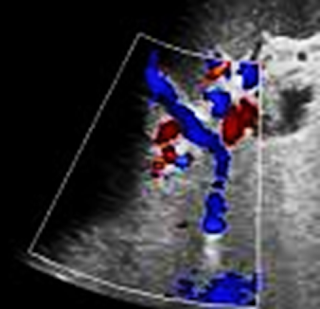

Doppler Ultrasound

• Non-invasive but operator-dependent.

• May show absent flow in the splenic vein or turbulent flow in collateral vessels.